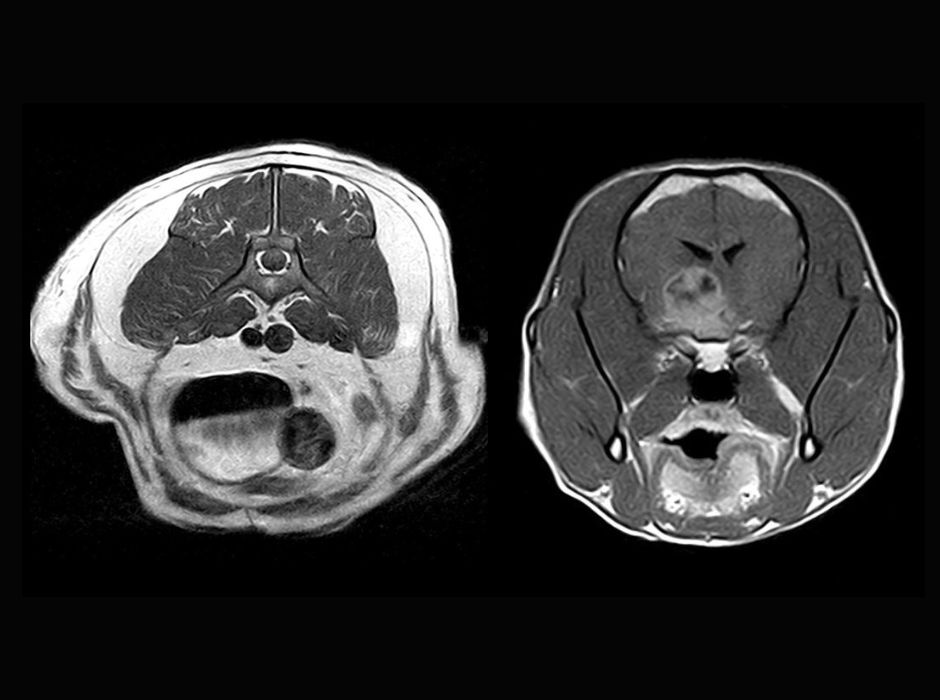

An MRI system should be specifically tailored to the needs of veterinary medicine – through dedicated coils, software, and ease of use. Fast and high quality images, as well as easy-to-learn operation are also important. And as you would expect, cost-effectiveness and small spatial requirements also play a major role.

We have been operating MRI in our clinic since 2003. Over the years, more optimised systems have been introduced, along with innovations and improvements in coils, software, and so on, which we have gladly adopted and want to continue to use. We chose the latest system because it is forward-looking and meets all our requirements, such as ease of handling and excellent, fast image quality. Above all, its cost-effectiveness once again convinced us, since the new system also benefits from very low operating costs thanks to its permanent magnet.

Thanks to detailed initial training and ongoing support, performing MRI examinations did not take long to learn, and Dr Sandra Gerhard, a specialised veterinary physician, has been part of our team since 2011. With the help of further training opportunities, specialised courses, and exchanges with other experts, knowledge and skills are being continuously improved. Thanks to specially designed coils and the open structure of the system, it is possible to position and examine animals of various types and sizes quite easily. We have benefited from excellent support here too.